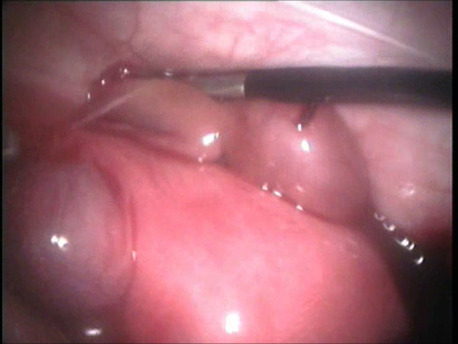

Endoscopy involves placing a small telescope into the human body through tiny incisions (3-5mm). The telescope can be placed into the abdomen via small tubes called ports (laparoscopy) or inside the uterus through the mouth of the uterus or cervix (hysteroscopy).

Various fine and delicate instruments are available through which complicated surgeries can be performed inside the abdomen or the uterus. In fact, endoscopic surgery has become the gold standard of surgery today. Since most of these instruments are being manufactured locally, the cost of endoscopy has also reduced significantly since its advent in the eighties.